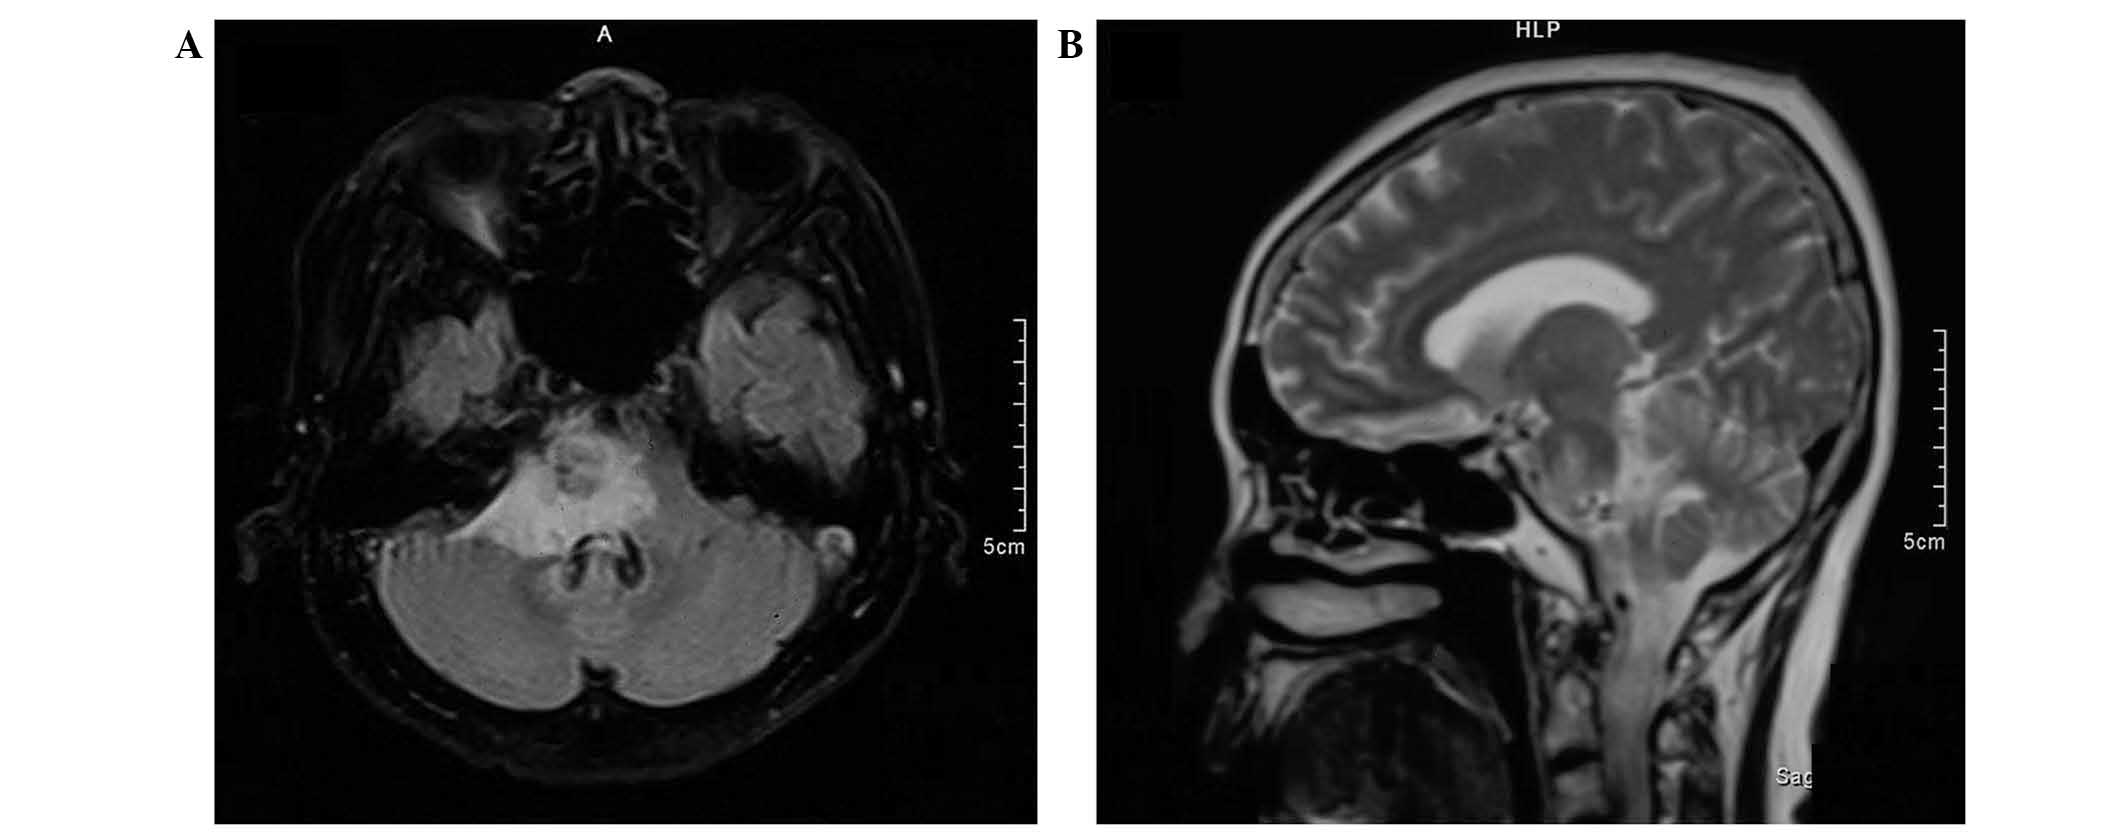

Brainstem metastases have a poor prognosis and are difficult to manage. The present study describes the first case of histopathologically‑confirmed brainstem metastasis originating from lung adenosquamous carcinoma, and discusses the outcomes of treatment by stereotactic aspiration combined with gamma knife radiosurgery (GKRS). A 59‑year‑old female presented with a cystic mass (15x12x13 mm; volume, 1.3 cm3) located in the pons, two years following surgical treatment for adenosquamous carcinoma of the lung. The patient received initial GKRS for the lesion in the pons with a total dose of 54.0 Gy, however, the volume of the mass subsequently increased to 3.9 cm3 over a period of three months. Computed tomography‑guided stereotactic biopsy and aspiration of the intratumoral cyst were performed, yielding 2.0 cm3 of yellow‑white fluid. Histology confirmed the diagnosis of adenosquamous carcinoma. Aspiration provided immediate symptomatic relief, and was followed one week later by repeat GKRS with a dose of 12.0 Gy. The patient survived for 12 months following the repeat GKRS; however, later succumbed to the disease after lapsing into a two‑week coma. The findings of this case suggest that stereotactic aspiration of cysts may improve the effects of GKRS for the treatment of cystic brainstem metastasis; the decrease in tumor volume allowed a higher radiation dose to be administered with a lower risk of radiation‑induced side effects. Therefore, stereotactic aspiration combined with GKRS may be an effective treatment for brainstem metastasis originating from adenosquamous carcinoma.

Figure 4